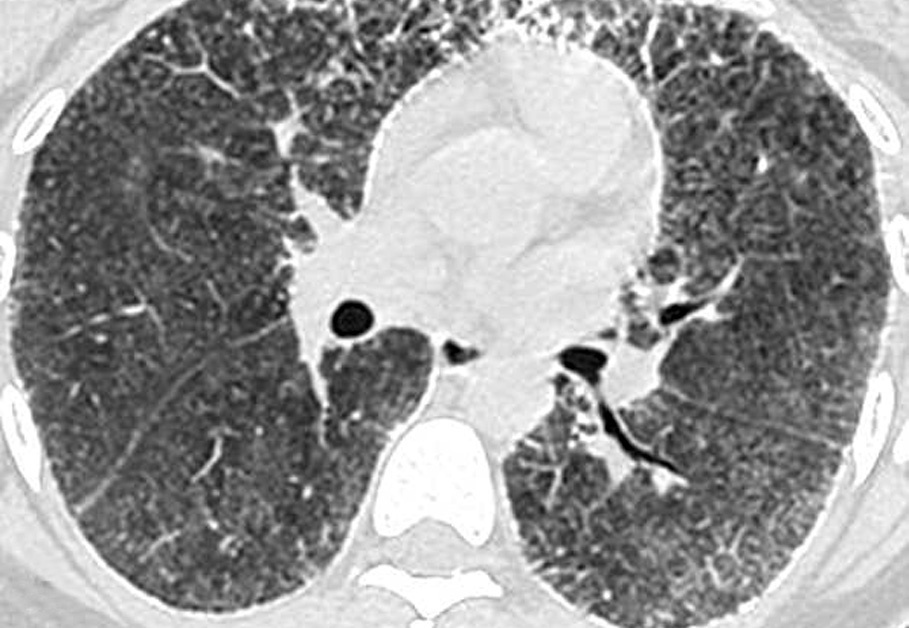

Las imágenes demostraron la presencia de puntiformes y difusas calcificaciones bilaterales, de predominio subpleural, en pleura mediastínica y en los septos interlobulillares. Los segmentos posteriores e inferiores estaban mayoritariamente afectos (fig. 2). También se visualizaron nódulos calcificados a nivel de segmentos anteriores (fig. 2B). El estudio detallado de alta resolución demostró un "patrón en empedrado" o crazzy-paving con marcado engrosamiento de los septos interlobulillares asociado a áreas parcheadas de aumento de la densidad en "vidrio deslustrado" o ground-glass, con mayor afectación de los segmentos posterobasales (figs. 3A y B). A nivel de los lóbulos superiores también se evidencian pequeños quistes subpleurales (fig. 3C).

Fig. 3. Las imágenes tomográficas de alta resolución demuestran la presencia de áreas mal definidas de aumento de densidad en vidrio deslustrado o ground-glass, con moderado engrosamiento de los septos interlobulillares, principalmente en los segmentos anteriores, adoptando en conjunto un "patrón en empedrado" o crazy-paving pattern (A). Secciones inferiores (B) demuestran la mayor afectación de las bases pulmonares. (C) También pueden visualizarse pequeños quistes subpleurales (flechas).

Las imágenes por TCAR15-22 muestran áreas de alta atenuación en "vidrio deslustrado" o ground-glass, con cierta predisposición por las bases pulmonares y segmentos posteriores. Parecen corresponder a cúmulos de microlitos inferiores a 1 mm, aunque también se pueden observar nódulos calcificados mayores de 1 mm15-20. Cuando estas áreas en vidrio deslustrado se asocian a engrosamiento de los septos, adoptan lo que se conoce como "patrón en empedrado" o crazy-paving pattern. Este hallazgo generalmente se ha asociado a patologías tales como la proteinosis alveolar y la neumonía por Pneumocystis carinii, entre otras21,22 y con menor frecuencia a la microlitiasis alveolar.